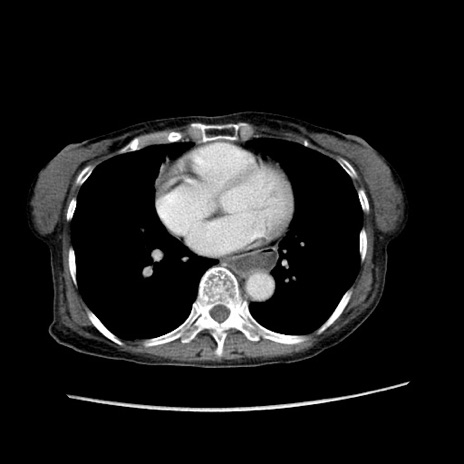

症例25(横断像)

【症例】80歳代女性

【主訴】胸のつかえ感

【現病歴】約9時間前に食後から胸のつかえた感じあり、嘔吐あり、来院。

【既往歴】胃癌(全摘)、胆摘、虫垂炎

【身体所見】心窩部に圧痛あり、反跳痛なし。

【データ】WBC 5700、CRP 0.05